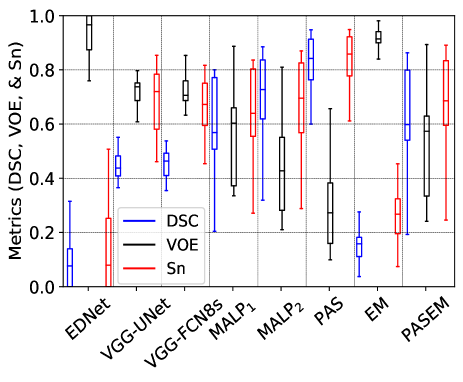

Fig. 7 exhibits the Box and Whisker visualization of all the methods showing the spreads and centers of the DSC, VOE, and Sn metrics for all the 20 test images, either CT or MRI scans.

The experimental results in Table III quantitatively demonstrate that the EDNet is the worst-performing method than the other two CNN-based methods, such as VGG-UNet and VGG-FCN8s, by the margins of and for CT scans and and for MRI scans, respectively, concerning the mDSC. Those two networks also defeat the EDNet for the other two metrics (mVOE and mSn) with significant margins (see in Table III). Although those three networks have the same number of convolutional and pooling layers in the encoder and decoder, they constructionally vary in skip connection employment (see details in subsection II-C). The results on both the imaging modalities reveal that the appliance of skip connection has outputted better-segmented substructures, as the local information from the shallower layers is utilized to reconstruct output masks through the skip connection (see the results in Table III). Again, it is seen from Fig. 7 that the DSC, VOE, and Sn from the EDNet are sparse for both the CT and MRI scans, with significantly fewer median metrics, which demonstrates that EDNet produces scattered results for each of the testing cases. On the other hand, the upper- and lower-whisker for all three metrics are closer for VGG-FCN8s and VGG-UNet than the EDNet (see in Fig. 7), which shows better-robustness of them comparing the EDNet.

Furthermore, the qualitative results in Fig. 8 depict that both the VGG-UNet and VGG-FCN8s provide better-segmented substructures of both the modalities (CT and MRI) than the EDNet. In some examples of the EDNet, none of the target substructures are segmented, which provide VOE as (see upper-whisker in Fig. 7 (b)). The encoders in all three networks have 13-convolutional and 5-pooling layers, where the in-depth features obtained from them have lost spatial location information due to pooling in the encoders. Hence, the output masks from EDNet have less local information, which is solved in the VGG-UNet and VGG-FCN8s due to the concatenation of local information through the skip connection, providing an alternative path for the gradient with backpropagation. It is experimentally validated in our investigations that the additional skipping paths are beneficial for improving the segmentation results of different heart substructures.

Again, it is also remarkable that VGG-FCN8s even exceeds the VGG-UNet (see the corresponding results in Table III, Fig. 7, and Fig. 8) by the margins of and respectively for CT and MRI scans in terms of mDSC. The former network further outperforms the latter network concerning the other two metrics, such as mVOE and mSn, with significant margins for the CT scans. The concatenation of low-level features from the encoder’s antecedent layers with the equivalent decoder scale in VGG-UNet is the possible reason for failing VGG-UNet than VGG-FCN8s [35, 16]. Unessentially, an aggregation of the corresponding scale feature maps from the beginning layer of the encoder, is observed as a weakness of the UNet, as it imposes an undesirable merging procedure, forcing aggregation barely at the corresponding scale feature maps of the encoder and decoder, which was similarly experimentally validated in [35] and our previous article for other medical imaging modality [16]. On the other hand, in VGG-FCN8s, we fuse the feature maps from the encoder’s different coarseness starting from the third block of the encoder, making it a winner of three implemented CNN-based WHS approaches.

III-A2 Results for MALP-based methods

The label propagated segmentation results utilizing different deformed atlas images are quantitatively and qualitatively manifested in Table III, Fig. 7, and Fig. 8. The median and MVF schemes of level propagation, as described in subsection II-B2, generate the heart segmentation results with the mVOEs of and , respectively, for CT scans and and , respectively, for MRI scans. Table III demonstrates that the MVF scheme outperforms the median method of MALP by the margins of and respectively for CT and MRI modalities for mDSC. The former MALP method also outperforms the latter MALP method with significant margins concerning the other two metrics (mVOE and mSn). The Box and Whisker visualization of all three metrics in Fig. 7 for both the methods demonstrate the superiority of the MVF scheme than the median strategy for both the imaging modalities. Fig. 8 (top) and Fig. 8 (bottom) exhibit the qualitative results respectively for CT and MRI scans for both the median (MALP1) and MVF (MALP2) schemes. Those results qualitatively confirm that the segmented substructures from MALP1 suffer from the outliers (see in fifth and sixth columns of Fig. 8), where most of the organs are erroneously labeled with other organs. All the experimental results reveal that the MVF scheme has better dealt with the outliers as it counts the majority of the labels from the voting candidates, whereas the median method estimates the median values of the counter, which may not be matched by the majority voters.

III-A3 Results for probabilistic atlas-based methods

The WHS results of the probabilistic atlas are exhibited in Table III, Fig. 7, and Fig. 8, where we employ our three methods, such as PAS, EM, and PAS+EM (see details in subsection II-B2). The PAS, EM, and PAS+EM schemes of probabilistic atlas provide the heart segmentation results with the mVOEs of , , and , respectively, for CT scans and , , and , respectively, for MRI scans. Table III exhibit that the PAS scheme exceeds the other two methods, such as EM and PAS+EM, by the margins of and for CT scans concerning the mDSC, respectively, whereas it also beats them by the margins of and for MRI scans, respectively, in terms of the mDSC. Similarly, the EM and EM+PAS are also defeated by the proposed PAS method for mVOE and mSn for both the chest imaging modalities with considerable margins (see in Table III). The spreads and centers of the DSC, VOE, and Sn metrics for all the 20 test images (either CT or MRI scans), as exhibited in Fig. 7, also reveal the supremacy of the proposed PAS method over the other two methods (EM and EM+PAS).